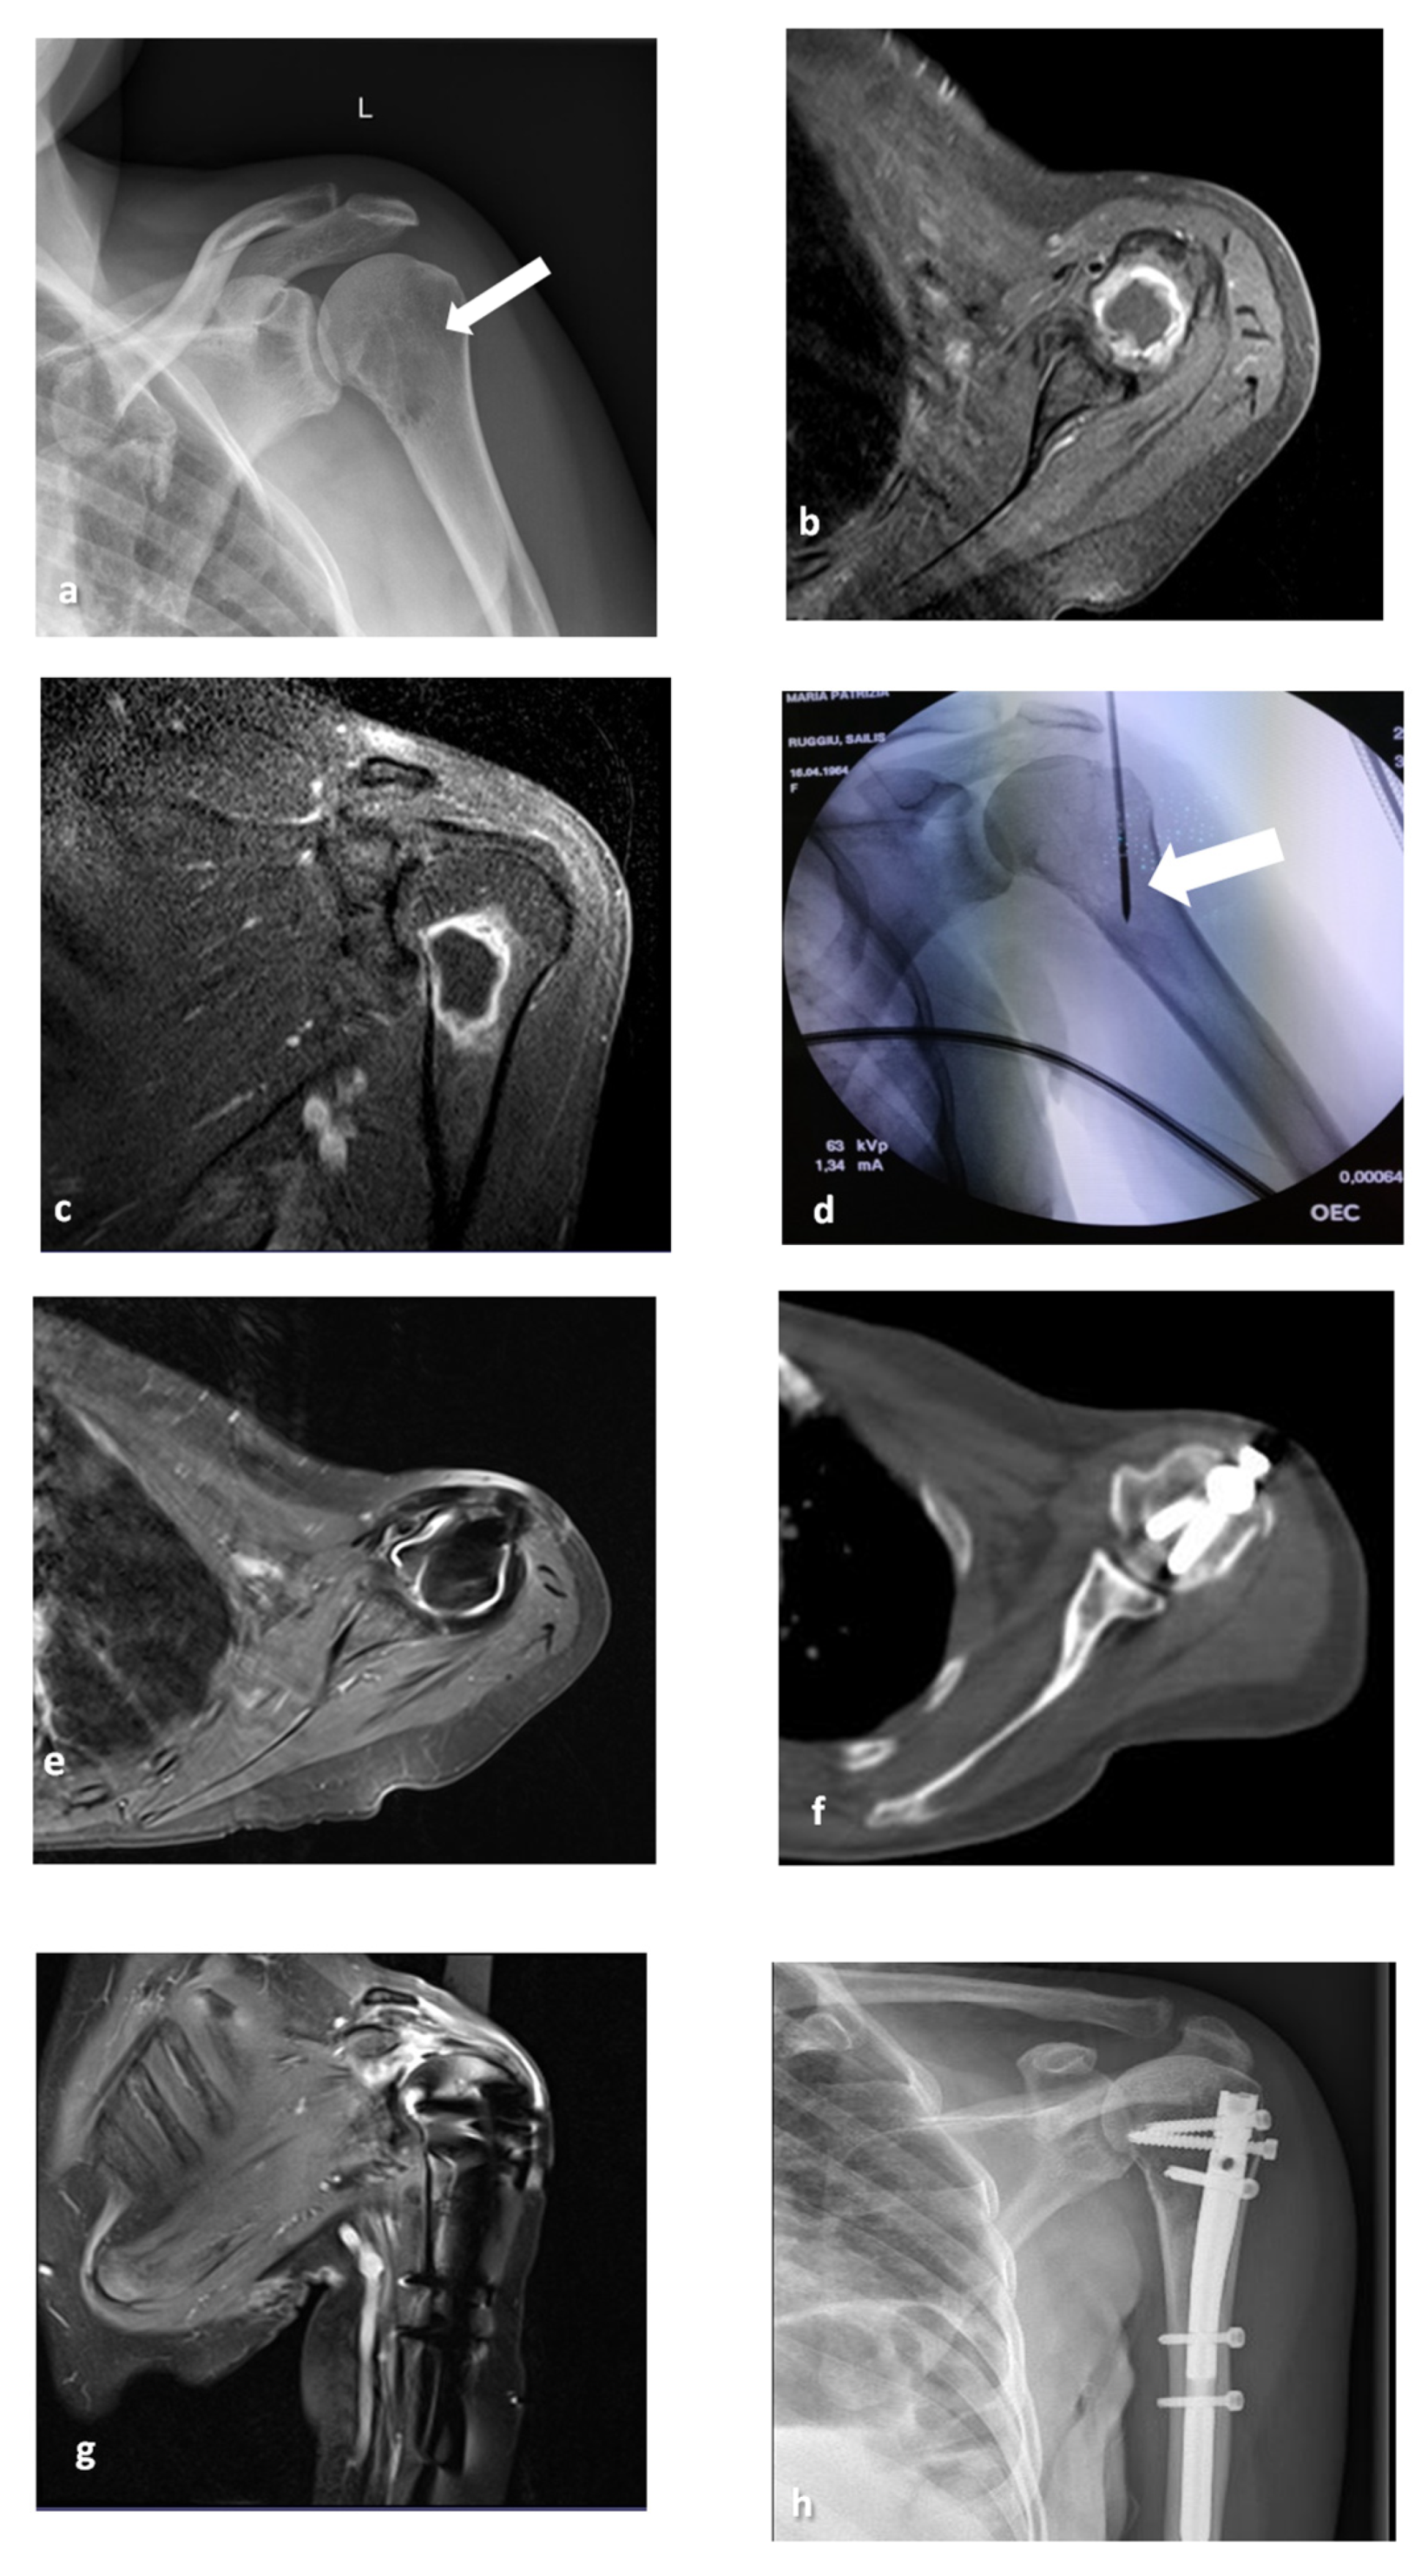

2. Materials and Methods

2.2. MWA Technique

2.3. Surgical Technique